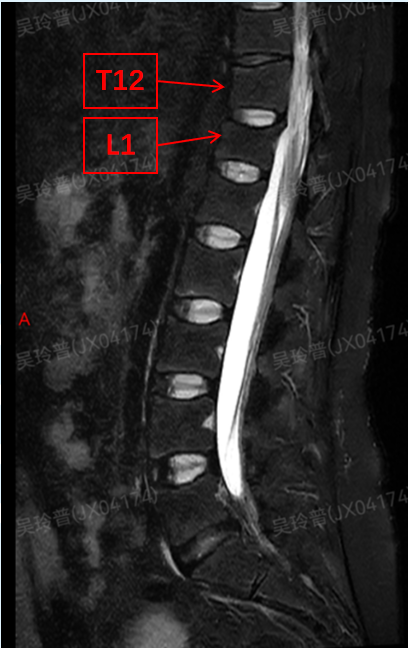

起初她以为是产后身体虚弱,没太在意,没想到4个月后按摩时疼痛突然加重,经MRI检查发现T12和L1椎体压缩性骨折。

后续骨密度检测更让人揪心:腰椎(1-4)骨密度仅0.544g/cm²,Z值低至-4.3,属于极高骨折风险,最终被确诊为“妊娠特发性骨质疏松伴有病理性骨折”。

△ 刘女士的腰椎磁共振检查中见到T12和L1椎体压缩性骨折